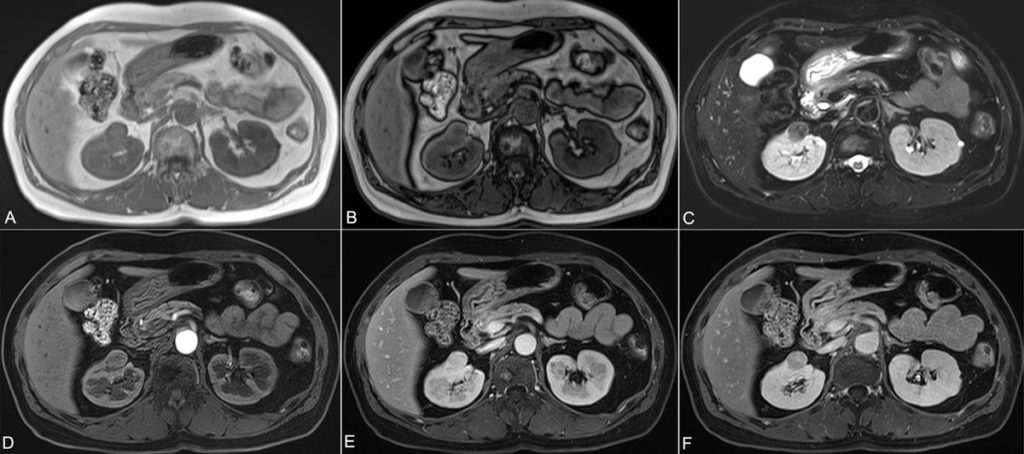

КТ — это диагностический метод, основанный на действии Х-лучей на органы и ткани. Для улучшения визуализации исследуемых структур в медицинской практике используют контрастные вещества, которые накапливаются в патологически измененных участках и образованных очагах.

Использование контрастных веществ улучшает качество картинки исследуемой области, дифференциацию анатомических образований, показывает участки патологического разрастания сосудов при опухолях.

Накопление препаратов в патологических участках дает четкое представление о локализации и кровоснабжении образования.

При злокачественных новообразованиях внутривенное контрастирование при МСКТ дает детальное описание образования, определяет особенности, взаимоотношение с окружающими тканями и стадию процесса.